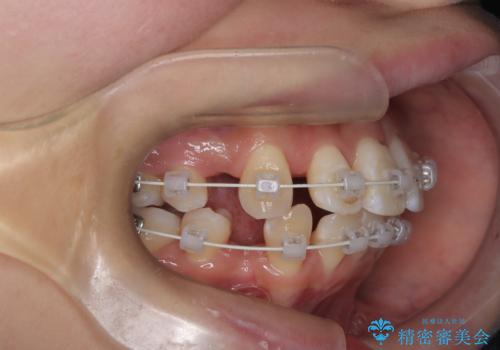

今回の矯正治療では、まず計画通り上下左右の小臼歯4本を抜歯し、八重歯や正中のズレを解消するための十分なスペースを確保しました。装置には、目立ちにくい白いブラケットとワイヤーを使用した審美ワイヤー矯正を採用。

八重歯: 突出していた八重歯を歯列内に誘導し、デコボコを解消しました。